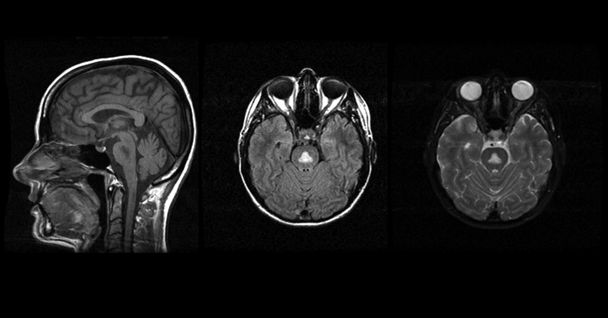

Central Pontine Myelinolysis (CPM)

A significant proportion of CPM cases (Goebel and Herman-Ben Zur 1976; Messert et al. 1979) include a history of alcoholism. People with CPM, which is associated with electrolyte disturbances and specifically with aggressive correction of low sodium levels in the blood (i.e., hyponatraemia) (Chua et al. 2002), may have symptoms such as the inability to control facial movements, decreased voluntary muscle control (i.e., ataxia), and acute changes in consciousness (Kumar et al. 2006; Pfister et al. 1985). Classically, CPM was characterized by the presence of a symmetric triangular or “bat-wing” lesion in the pons (DeWitt et al. 1984; Gerard et al. 1987), with hypointense T1-weighted (Kleinschmidt-Demasters et al. 2006; Martin and Young 1995) and hyperintense T2-weighted (Buis and Wijdicks 2002; Kleinschmidt-Demasters et al. 2006; Pfister et al. 1985; Martin and Young 1995) images (see figure 4) reflecting damage to the protective covering of nerve cells (i.e., demyelination) as noted postmortem (Goldman and Horoupian 1981). The term osmotic myelinolysis (e.g., Chua et al. 2002; de Souza and Desai 2012) was coined to reflect the fact that other brain regions (e.g., basal ganglia, thalami, and cerebral gray–white matter junctions) are affected in CPM (e.g., Chen et al. 1996; Graff-Radford et al. 2011; Hagiwara et al. 2008; Harlan et al. 1988; Price et al. 1987; Waragai and Satoh 1998), despite suggestions that pathology in these other regions may not strictly represent demyelination (Kleinschmidt-Demasters et al. 2006; Kumar et al. 2006). Because a postmortem study of 112 autopsy cases of CPM patients reported that 28 percent could also be diagnosed with WE (Goebel and Herman-Ben Zur 1976), pontine dysfunction should be regarded as a cardinal clinical sign of CPM.

Alcoholic Cerebellar Degeneration (ACD)

ACD patients most frequently display ataxia, although other symptoms can include uncontrollable and repetitive eye movement (i.e., nystagmus) and speech problems resulting from impaired muscle control (i.e., dysarthria) (Fitzpatrick et al. 2012). Neuroimaging in ACD demonstrates damage disproportionately apparent in anterior superior portions of the cerebellar vermis (Sullivan et al. 2000a), with postmortem pathology indicating loss of cerebellar Purkinje cells (Feuerlein 1977).